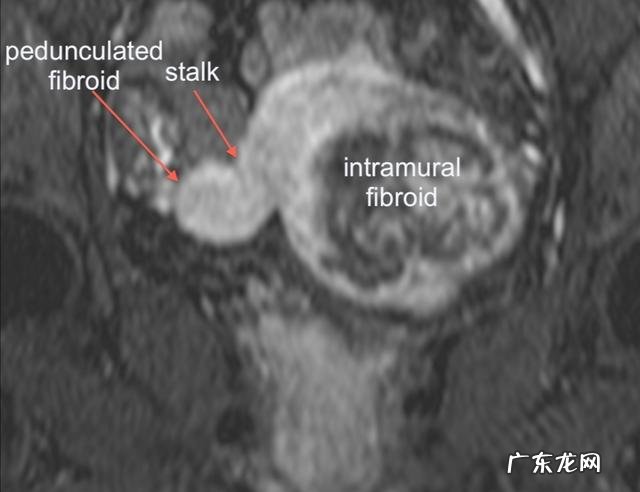

第二种,叫做浆膜下子宫肌瘤 。这是一种从子宫肌壁往外长的,就是像大家的肚子里面长的,下面有一根带着我们的子宫,这种肌瘤占了所有子宫肌瘤的20%左右;